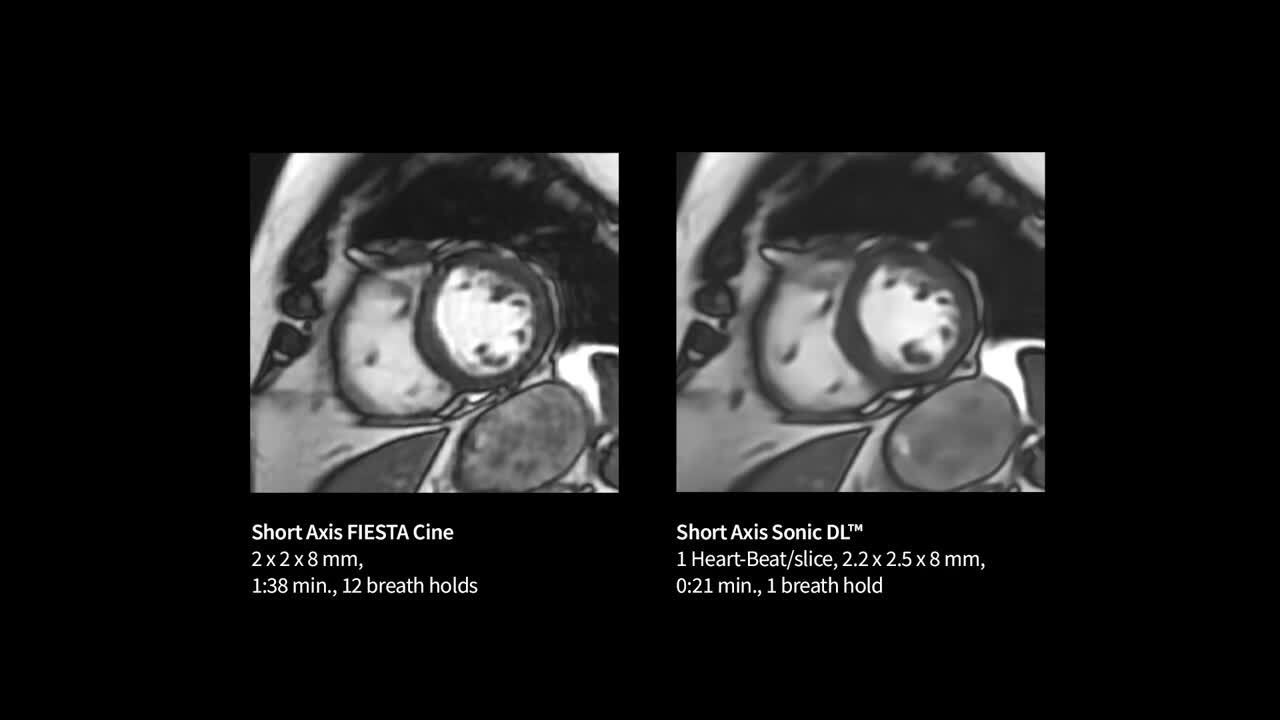

Life-Speed imaging

Achieve up to 12X acceleration and up to 83% scan time reduction*